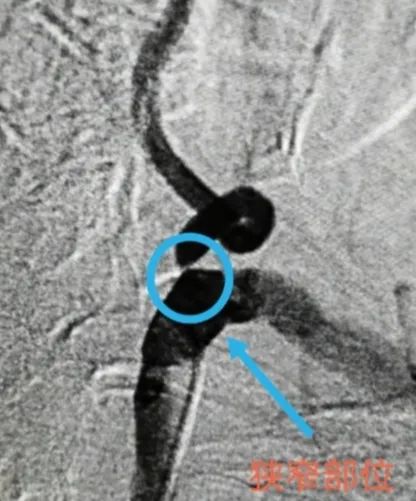

术前↓:造影显示椎动脉狭窄部位